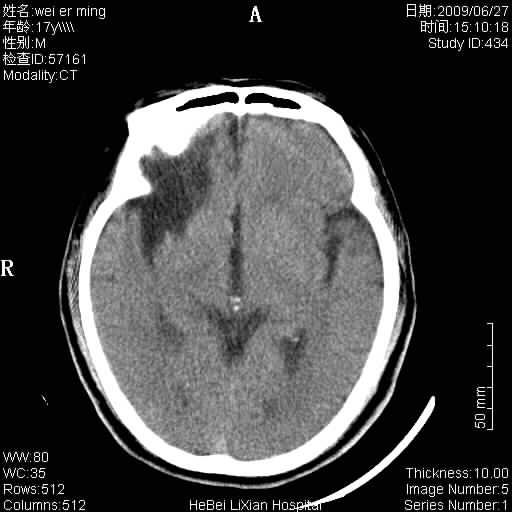

标题: CT20838:帮忙看看,是软化灶吗?

患者,男,67岁.既往有脑血栓病史.若是软化灶里面怎么出现钙化呢?

脑软化灶伴灶内钙化,钙化可能是梗塞后出血,出血钙化.

支持软化灶伴穿通畸形,钙化为胶质增生、机化、钙化。

支持 右侧额叶软化灶伴脑穿通畸形(钙化为胶质增生、机化、钙化)。

是脑软化灶,其内的钙化可解释为闭塞血管内的血栓钙化。

脑梗塞后形成的软化灶内可以有钙化密度影,系血管出血机化或血管内血栓钙化所致。